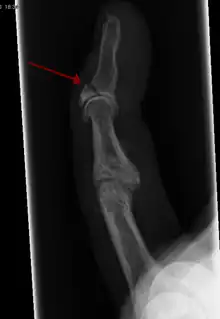

![]() | |

| Avulsion fracture of the proximal middle phalanx on the palm side | |